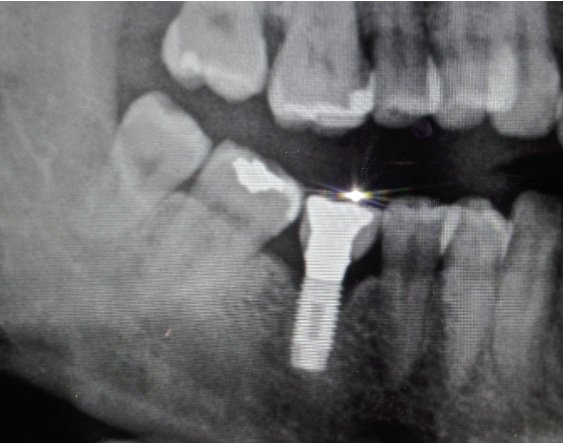

Buenas compañeros me podriais ayudar con la marca del implante del 36? y tambien con el destornillador y compatibilidades, muchas gracias